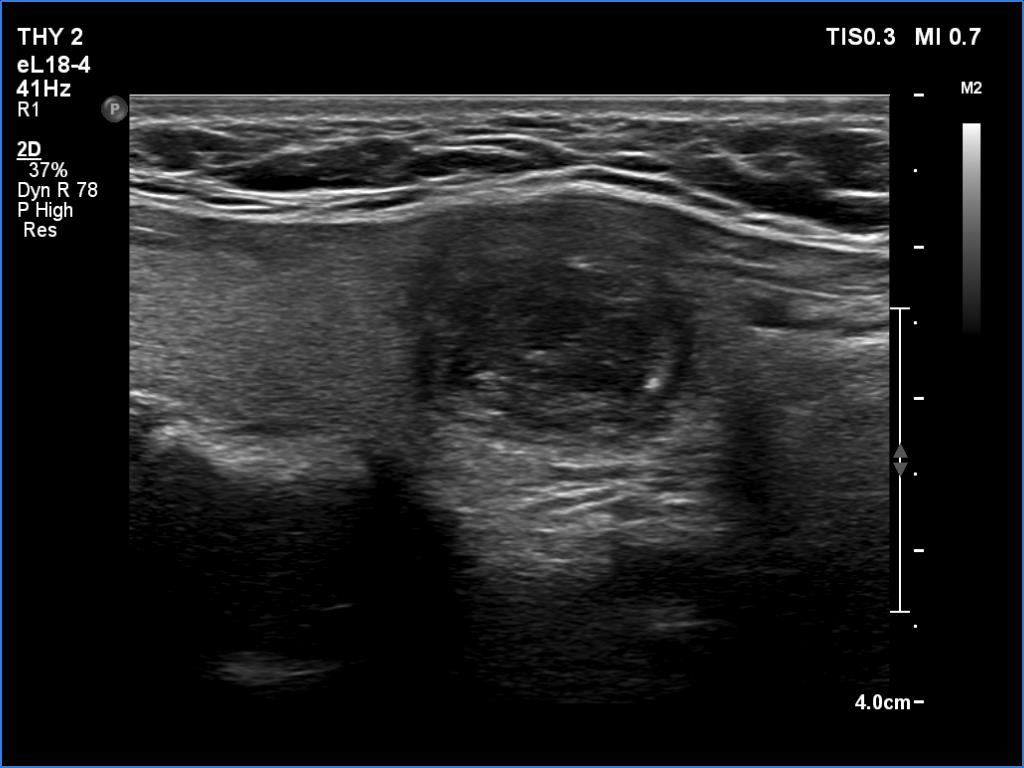

Ultrasonography revealed an echonormal thyroid. There was dominantly moderately hypoechoic nodule in the right lobe. Some parts of the lesion were deeply hypoechoic, and a few small cystic chambers were also within. The nodule presented with irregular shape and borders and had intranodular echogenic figures, primarily granules.

It is ambiguous how to interpret the echogenic figures. Although the presence of irregular shape and borders increases the likelihood that the echogenic granules are indeed microcalcifications, comet-tail artifacts must be also considered.

It is worth comparing the images recorded by using different settings. By using harmonization, we lose the details of very hypoechoic areas. Essentially, the latter seem to be anechoic.